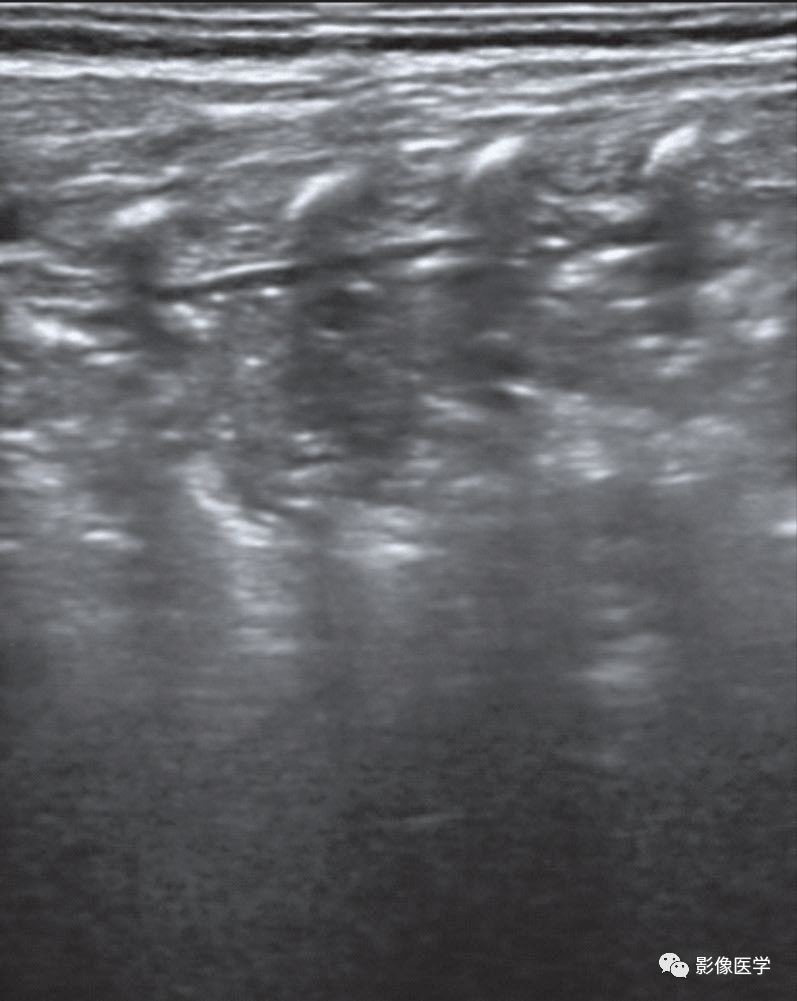

图 6-22 感染性肺炎(1)

胎龄35周,出生体重2 050g。因发热、呼吸困难2d于出生后1周入院。肺部听诊闻及密集湿啰音,血常规中性粒细胞比例及CRP均明显升高。胸部X线检查结果呈肺炎改变。肺脏超声显示右肺大面积实变伴支气管充气征,实变区边缘呈锯齿状,A线消失,胸膜线连续性中断或消失,同时可见极少量胸腔积液。